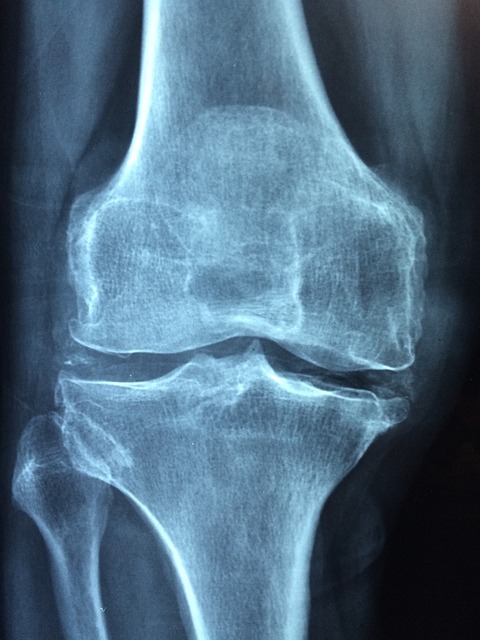

관절염

관절염은 관절에 염증을 일으키는 만성 질환입니다. 골관절염, 류마티스 관절염 및 통풍을 포함하여 무릎 관절에 영향을 줄 수 있는 여러 유형의 관절염이 있습니다. 관절염은 무릎 관절에 통증, 부기 및 뻣뻣함을 유발할 수 있습니다.